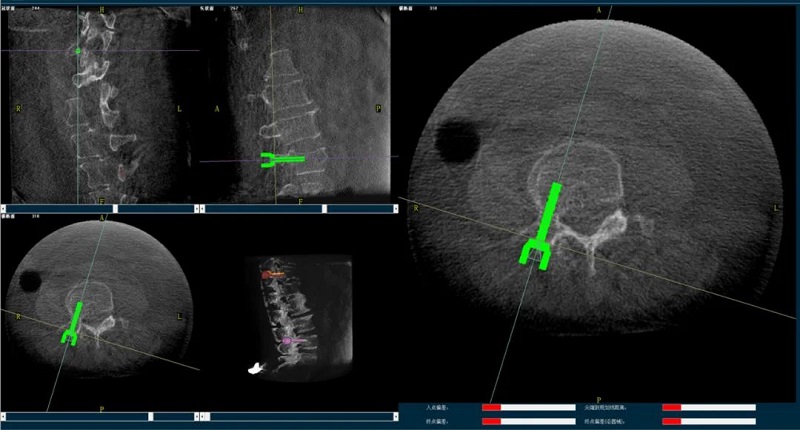

(四)圖像可視化

一旦圖像配準(zhǔn)完成,手術(shù)導(dǎo)航系統(tǒng)會(huì)將手術(shù)器械的虛擬圖像與術(shù)中獲取的三維影像進(jìn)行重疊顯示。隨著醫(yī)生移動(dòng)真實(shí)的手術(shù)器械,其對(duì)應(yīng)的虛擬圖像也能在三維CT影像上實(shí)現(xiàn)實(shí)時(shí)同步移動(dòng)。

通過觀察手術(shù)導(dǎo)航系統(tǒng)的屏幕,醫(yī)生能夠?qū)崟r(shí)地掌握器械與患者手術(shù)部位的解剖結(jié)構(gòu)的相對(duì)位置關(guān)系。這一信息至關(guān)重要,它幫助醫(yī)生精確評(píng)估手術(shù)器械與目標(biāo)手術(shù)點(diǎn)的距離,從而沿著預(yù)先規(guī)劃的手術(shù)路徑,精準(zhǔn)地進(jìn)行手術(shù)操作。